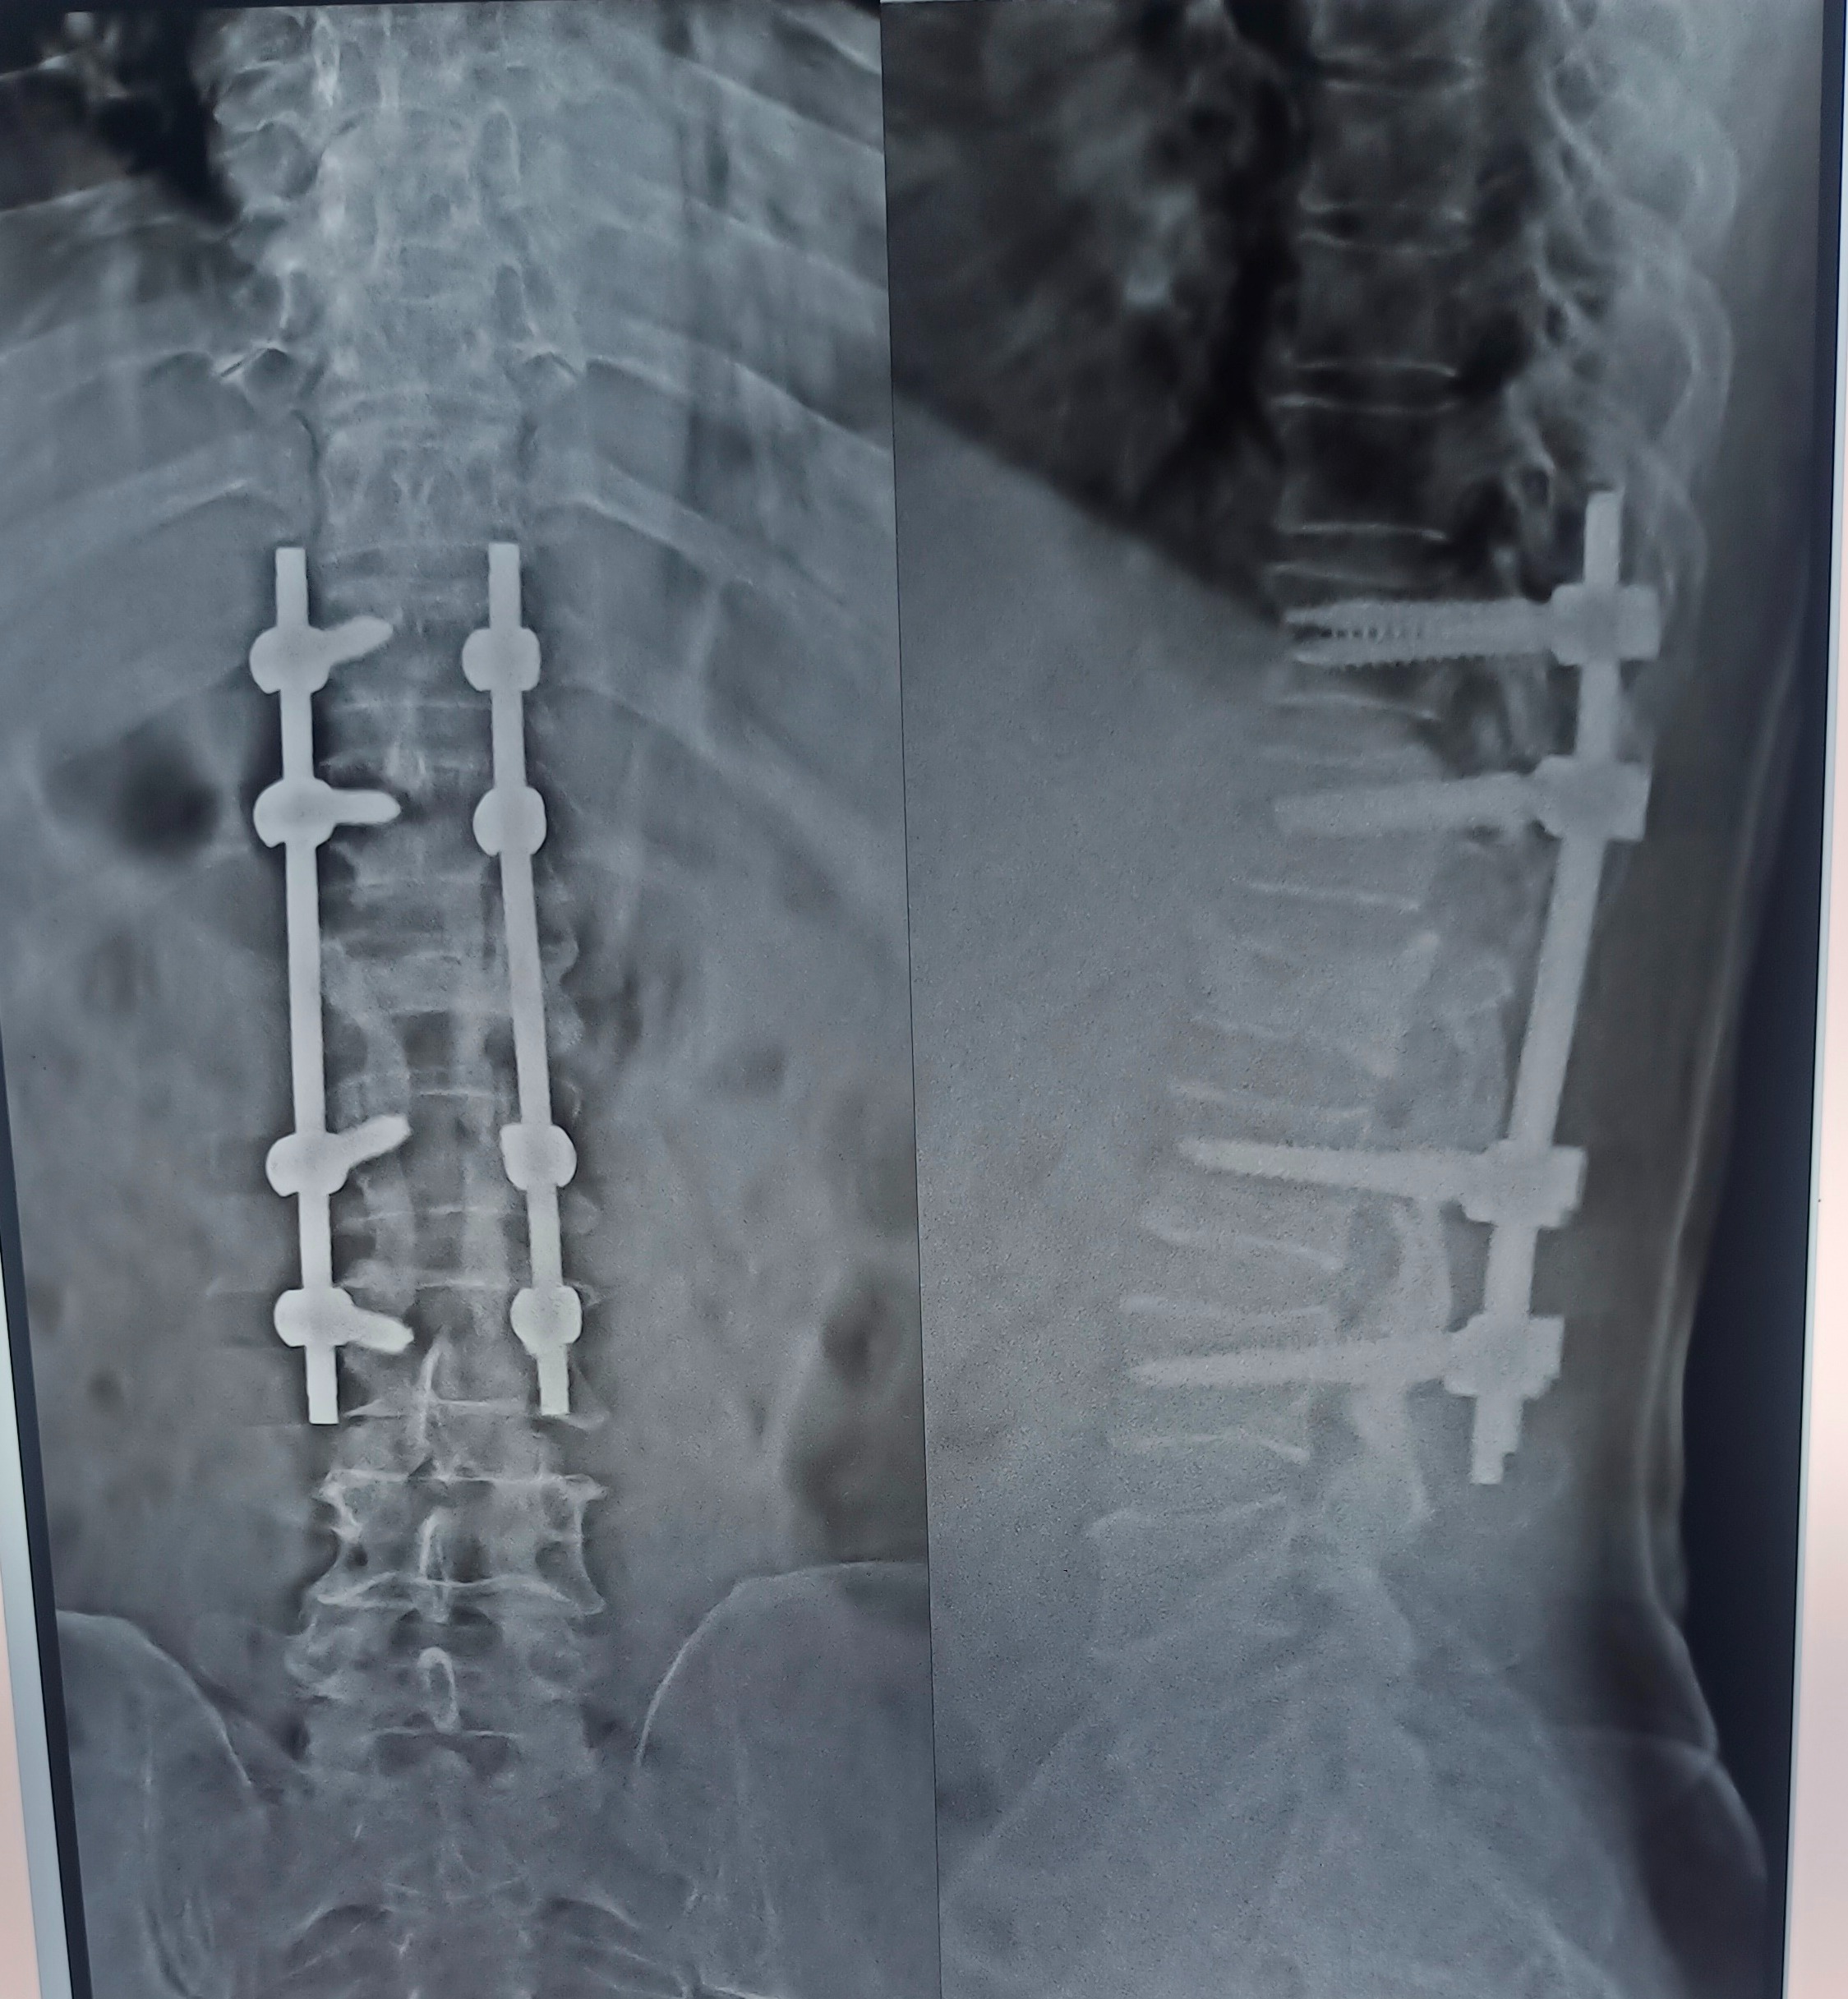

BEST SPINE DOCTOR IN PUNE BEST SPINE SPECIALIST IN PUNE BEST SPINE SURGEON IN PUNE ORTHOPEDICA DN SPINE CLINIC IN PUNE MEET DR. NITISH AGARWAL AGARWAL SPINE CLINIC FC ROAD THIS PATIENT WAS OPERATED FOR SPINE FRCATURE 1 YEAR BACK. SPINE FIXATION WITH RODS AND SCREWS WAS DONE TO STABILISE THE SPINE. DECOMPRESSION LAMINECTOMY WAS ALSO DONE TO DECOMPRESS THE SPINE. SINCE LAST 1 YEAR PATIENT IS DOING REGULAR EXERCISES AND TAKING CALCIUM AND VITAMIN SUPPLIMENTS. NOW AFTER 1 YEAR PATIENT IS COMPLETLY PAIN FREE. AT THE AGE OF 75 HE IS STILL GOING TO HIS OFFICE AND DOING 4-5 HOURS OF WORK.